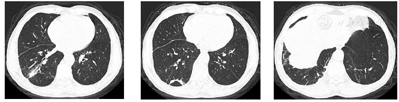

患者肺脓肿并多房包裹性脓胸诊断明确。于11月3日在CT引导下行包裹性脓胸穿刺(图7)及置管引流(图8)术。穿刺处胸水常规:深黄色、微浊胸水,无凝块,白细胞总数29×106/L,单个核细胞31%,多个核细胞69%,红细胞0×109/L,李凡他实验+;胸水生化:白蛋白25.5 g/L,球蛋白17.7 g/L,总蛋白43.2 g/L,淀粉酶40 U/L,葡萄糖7.01 mmol/L,乳酸脱氢酶556 U/L,腺苷脱氨酶17.91 U/L。胸水检验结果支持肺炎旁胸腔积液。置管处胸水常规:黄色、浑浊胸水,无凝块,白细胞总数100803×106/L,单个核细胞15%,多个核细胞85%,红细胞38×109/L,李凡他实验+++;胸水生化:白蛋白26.4 g/L,球蛋白23.6 g/L,总蛋白50 g/L,淀粉酶30 U/L,葡萄糖0.03 mmol/L,乳酸脱氢酶7020 U/L,腺苷脱氨酶130.15 U/L;胸水培养(需氧菌+厌氧菌)阴性;未查见抗酸杆菌。引流出脓性胸水约200ml(图9)。胸水检验结果支持脓胸。复查红细胞沉降率102 mm/h;血常规:白细胞计数11.9×109/L,中性粒细胞绝对值9.15×109/L,血红蛋白103 g/L,中性粒细胞百分率76.9%;C反应蛋白260.45 mg/L;肝功能:白蛋白33.5 g/L,直接胆红素26.2 umol/L,总胆红素32.4 umol/L,总胆汁酸17 umol/L;降钙素原0.69 ng/ml。予生理盐水和碳酸氢钠反复冲洗脓腔、尿激酶(1万U,1次/d)胸腔内注射,同时给予人血白蛋白静脉滴注以纠正低蛋白血症。复查胸部彩超提示右侧胸腔包裹性积液,积液黏稠,周围壁及分隔较厚。复查胸部CT(图10、图11)示:右肺上叶后段、右肺中叶及下叶多发感染并右肺下叶肺脓肿形成,右肺感染较前有所吸收;右侧胸腔引流术后,右侧胸腔积液、积脓较前吸收减少;右侧胸膜增厚。于11月8日再次在CT引导下行包裹性脓胸穿刺术。患者临床症状逐渐改善,11月17日复查红细胞沉降率96 mm/h;血常规:白细胞计数7.89 ×109/L,中性粒细胞绝对值4.53×109/L,血红蛋白104 g/L,中性粒细胞百分率57.4%;C反应蛋白25.75 mg/L;白蛋白40.8 g/L;降钙素原正常。11月22日复查胸部CT(图12,图13):右肺下叶见片状、不规则状密度增高影,部分可见液化坏死,较前片吸收好转;右肺底局限性包裹性积液;双肺下叶、右肺中叶感染;右侧胸膜弥漫性增厚,右侧胸腔包裹性积液;右侧斜裂少许包裹性积液;纵隔淋巴结肿大。11月23日复查红细胞沉降率60 mm/h;血常规:白细胞计数5.57×109/L,中性粒细胞绝对值2.76×109/L,血红蛋白106 g/L,中性粒细胞百分率49.6%;C反应蛋白11.93 mg/L;电解质正常。患者病情好转于11月24日出院,继续口服莫西沙星和甲硝唑抗感染治疗1个月。

12月24日复查胸部CT提示双肺感染、右肺下叶脓肿较前片吸收;右肺底局限性包裹性积液、右侧胸腔包裹性积液和右侧斜裂少许包裹性积液较前片减少(图14、图15)。2022年3月2日患者来院复诊,诉体重增加约5 kg,无明显不适,复查胸部CT(图16,图17,图18)提示右下肺脓肿已吸收,双肺下叶慢性感染、纤维化灶。